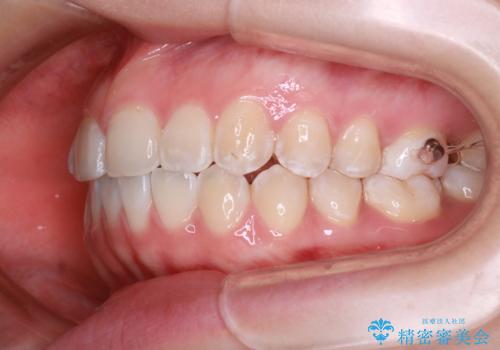

- 他院で矯正治療を受けていた患者様が、より理想的な仕上がりを求めて転院されました。主なお悩みは正中(前歯の中心)がズレていることで、歯並び全体をきれいに整えたいとのご希望でした。治療には舌側(裏側)に装置を装着するフルリンガル矯正を採用し、さらにアンカースクリューを用いて奥歯を後方へ移動(遠心移動)させることでスペースを確保し、正中を調整する計画を立てました。

矯正装置を装着し、アンカースクリューを活用しながら奥歯を少しずつ後ろへ動かし、正中を整えていきました。治療には時間がかかりましたが、計画通りに歯を移動させ、バランスの取れた歯並びへと仕上げることができました。裏側矯正のため、見た目を気にすることなく治療を進められた点も、患者様にとって大きなメリットでした。治療後は、「正中がしっかり合って、口元がスッキリした」とご満足いただきました。